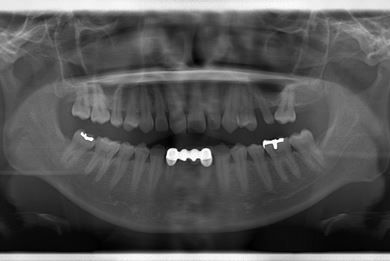

| 性別/年齢 | 女性 / 28歳 | ||||||||||||||||||||||||||||||||

| 主訴 | 下前歯の色が気になるので、ホワイトニングかセラミック治療できれいにしたい。(下前歯2本は乳歯でした) | ||||||||||||||||||||||||||||||||

| 治療方針 | 下顎前歯、乳歯を抜歯し、セラミック治療にて審美的回復を行う。 | ||||||||||||||||||||||||||||||||

| 治療内容 | エンプレスジルコニアフレームオールセラミッククラウンブリッジ4本 | ||||||||||||||||||||||||||||||||